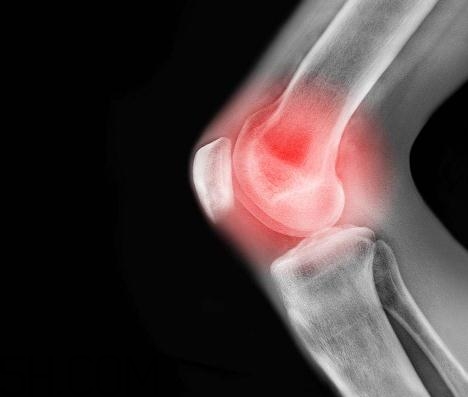

關(guān)節(jié)炎能吃螃蟹嗎?關(guān)節(jié)炎能吃海鮮嗎?

患有關(guān)節(jié)炎的人在飲食上面要特別注意,很多東西都會(huì)加重病情,要注意忌口。今天5號(hào)網(wǎng)小編給大家講講關(guān)節(jié)炎能吃螃蟹嗎?關(guān)節(jié)炎能吃海鮮嗎?

螃蟹性寒,一般關(guān)節(jié)炎患者忌食海鮮類食物,這其中自然包括螃蟹。尤其是風(fēng)濕性關(guān)節(jié)炎和類風(fēng)濕關(guān)節(jié)炎患者,更加要避免吃海鮮類,在關(guān)節(jié)炎的急性發(fā)作期、關(guān)節(jié)紅腫灼熱時(shí),更加不宜吃螃蟹,也不宜吃海鮮。

海鮮類的食品是需要風(fēng)濕性關(guān)節(jié)炎的患者忌口的,患者不宜多吃海產(chǎn)品,海產(chǎn)品含有尿酸,被人體吸收后,能在關(guān)節(jié)中形成尿酸鹽結(jié)晶,使風(fēng)濕性關(guān)節(jié)炎的癥狀加重。

海鮮中含有大量的血尿酸,人如果吃了大量的海魚、螃蟹、海菜等海味,就會(huì)導(dǎo)致體內(nèi)血尿酸的代謝紊亂。血尿酸過多又排泄不出的話,就會(huì)在關(guān)節(jié)部位形成尿酸鹽結(jié)晶,使關(guān)節(jié)炎的癥狀更加嚴(yán)重,甚至引發(fā)痛風(fēng)。因此,關(guān)節(jié)炎患者忌多吃海鮮。